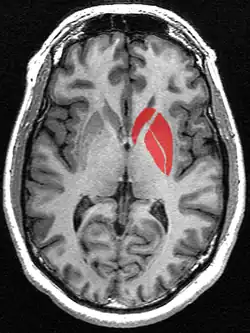

![]() Putamen (in red) shown within the brain | |